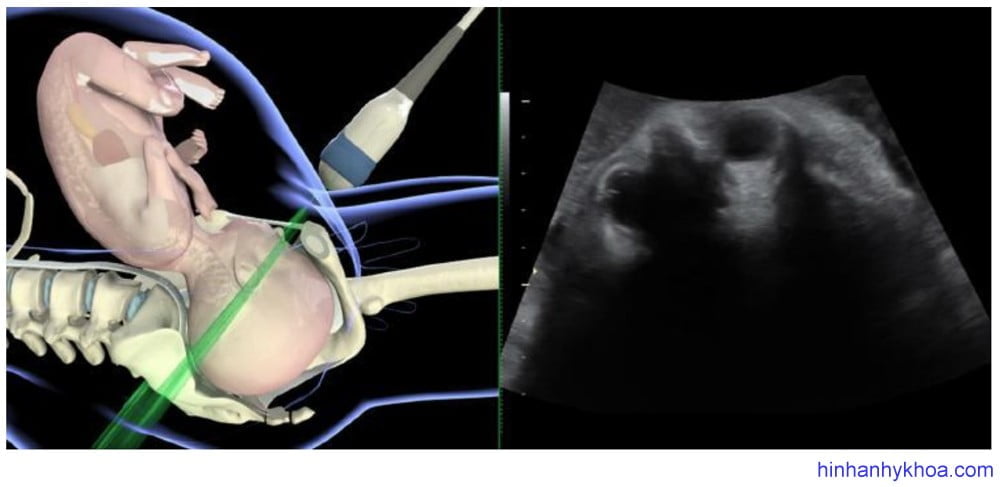

Siêu âm đánh giá kiểu thế thai được thực hiện tốt nhất qua ngã bụng ở mặt cắt ngang và đứng dọc. Đầu dò được đặt nằm ngang trên bụng mẹ, lấy mặt cắt ngang qua phần bụng trên hoặc ngực của thai, từ đó xác định vị trí cột sống. Sau đó di chuyển đầu dò xuống đến vùng trên xương mu của mẹ để thấy được đầu thai. Điểm mốc để xác định vị trí chẩm đó là nếu thấy hai hốc mắt thai có nghĩa là kiểu thế chẩm sau, thấy đường echo dày dọc giữa hai

bán cầu não là kiểu thế ngang, thấy vùng chẩm và cột sống cổ là kiểu thế trước [81] (Hình 1 và 2). Đám rối mạch mạc hai bên thường phân kì hướng về phía chẩm, cũng hữu ích trong việc xác định kiểu thế [47].

Hình 2: siêu âm ngã bụng mặt phẳng ngang cho thấy kiểu thế chẩm sau (Youssef và cs. [81])